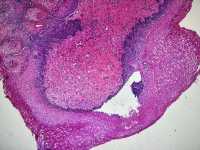

CIN1?

图1

图2

图3

图4

LSIL。

其实lsil的诊断一致性很低,上海的标准诊断lsil比较严格,似是而非者为非,本例属于似是而非,按我们的日常则争议比较多,我觉得综合看吧,阴道镜表现,hpv和tct检测结果来综合判断。

谢谢各位老师,TCT报ASCUS,患者自述HPV59阳